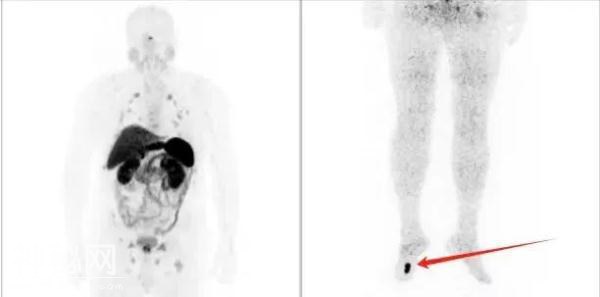

68Ga-DOTATATE PET/MR全身显像示:右侧足底高摄取结节

揪出了致病“元凶”——右侧足底肿瘤

倾向是磷酸盐尿性间叶性肿瘤

肿瘤仅“蚕豆”大小